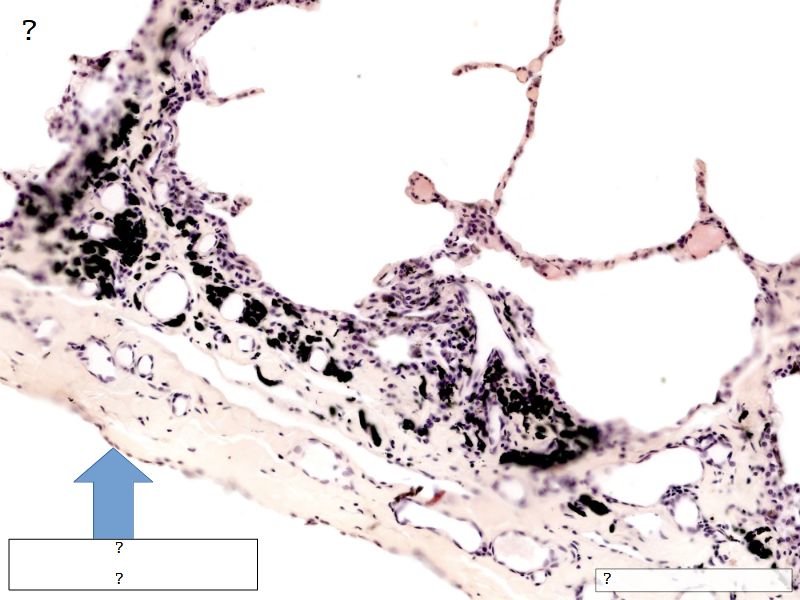

Fill in all the missing labels, and assess as you move through the slides. Answers on the down slide. It is important to do this using pen and paper, and not just glance through the images.